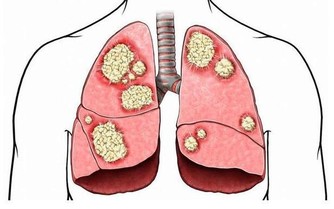

■ 出汗好處1/排除體內毒素廢物

當一個人長期不出汗時,就會「中毒」,因為身體,尤其是血液裡的很多毒素廢物,不能全部經由大小便排出去,必須依靠出汗來排泄。中醫稱「汗為心之液」,來源於血,作為人體最深層廢物的血液垃圾,主要就是透過出汗──人體最表層的方式,直接排出體外。一個人要是不能正常地出汗,廢物混在血液裡排不掉,必然會搗亂作怪,而且可能打「游擊戰」—從一個臟腑,跑到另一個臟腑去,打一槍換一個地方,那就很難對付,會引起大麻煩。